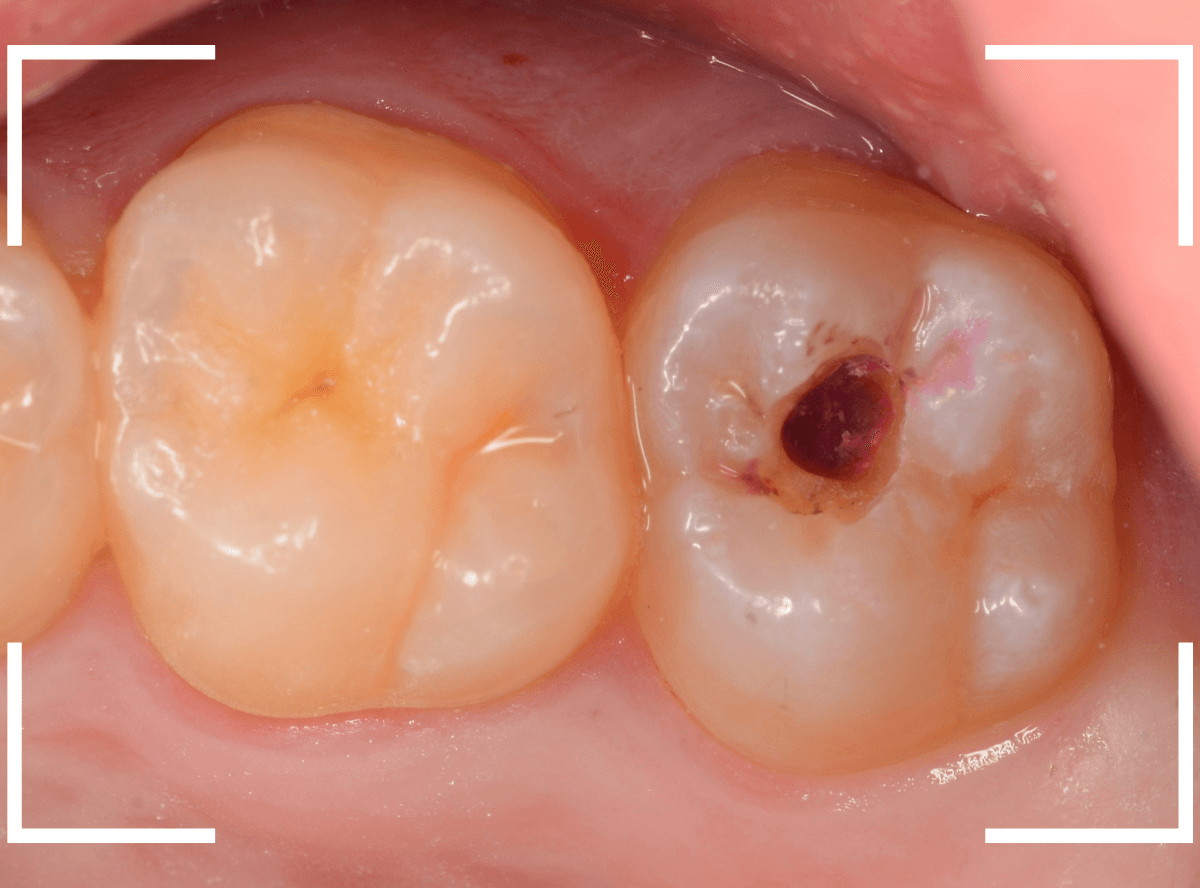

Case.5 症状もなく、神経の近くまで深く広がっている小窩裂溝う蝕

今回は、症状もなく、見た目には小さく見える、小窩裂溝う蝕の例です。

レントゲン写真で確認すると、今回はとても大きな虫歯になっている事が確認出来ました。

かなり神経の近くまで虫歯が進行しているのがわかります。

裂溝部分を少し削ると、中は虫歯で大きな空洞になっていました。